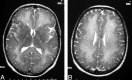

Hypoxic ischemic encephalopathy may cause early deep white matter abnormalities on MR imaging that usually progress to include gray matter and basal ganglia change. Toxic leukoencephalopathy due to heroin inhalation predominantly causes cerebellar and posterior cerebral radiologic change. Both conditions rarely present clinically and radiologically in a delayed manner with subsequent recovery. We report a case of reversible delayed posthypoxic/toxic leukoencephalopathy with no clinical or radiologic evidence of gray matter insult.